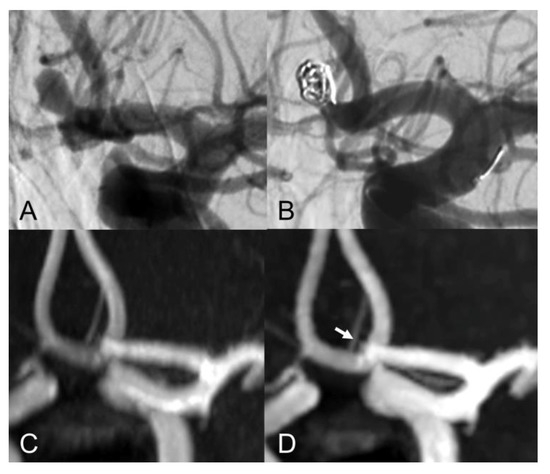

The evaluation of Class I - III coiled aneurysm occlusion status, with CS and PI TOF, is exemplified in Figure 1, Figure 2 and Figure 3.

Figure 1.

Anteroposterior view of vertebral artery digital subtraction angiography (DS) with (A) and without subtraction (B) after basilar-tip aneurysm coiling. Coronal MIP images of CS TOF (C) and PI TOF (D) showing complete occlusion of the aneurysm (class I). The interface between blood flow and coils is sharper on CS TOF images compared to PI TOF.

Figure 2.

Lateral view of internal carotid artery DSA before (A) and after (B) anterior communicating artery aneurysm coiling. Coronal MIP images of PI TOF (C) showing complete occlusion of the aneurysm (class I) and CS TOF (D) better depicting a tiny neck residue (arrow), which was nonetheless correctly graded as class II only by the interventional neuroradiologist.

The inter-modality agreement of CS and PI TOF MRA in the evaluation of aneurysm occlusion was perfect (κ = 1.00, p < 0.001) for all examiners except one, which classified one anterior communicating artery aneurysm as Class I on PI TOF images and as Class II on CS TOF images (Figure 2), leading, nonetheless, to an almost perfect inter-modality agreement (κ = 0.90, p < 0.001). The overall inter-modality agreement between the two techniques, considering all the readings by all the examiners (n = 88) was almost perfect (κ = 0.98, p < 0.001). No significant differences in inter-modality agreement were noted between patients who underwent coiling and stent-assisted coiling (κ = 1.00 and κ = 0.97, respectively). The overall inter-rater agreement was substantial (κ = 0.70, p < 0.001) and was almost identical for both CS TOF (κ = 0.71, p < 0.001) and PI TOF MRA (κ = 0.68, p < 0.001); 12 aneurysms (54.5%) were evaluated by all the examiners as completely occluded on both MRA techniques.

Our findings are in agreement with previous studies which showed comparable results between CS TOF and PI TOF MRA in the detection of a variety of cerebrovascular pathologies, including aneurysms, stenosis and arteriovenous shunts [21,22,23,24,25]. In particular, no significant differences were found between CS TOF and PI TOF MRA in the depiction of intact aneurysms, as well as in the measurement of neck, height and width of aneurysms [22]. In our study, only one case received a different occlusion classification in CS and PI TOF images, by the neurointerventionalist reader, who correctly appreciated a small neck remnant in CS TOF images, which was not apparent in the PI sequence (Figure 2). Therefore, while magnetic susceptibility artifacts due to the presence of the coil cast seem to have a comparable effect on both sequences in the majority of cases, we observed a sharper interface between blood flow and surrounding coils in some CS TOF images compared to PI TOF counterparts (Figure 1, Figure 2 and Figure 3).